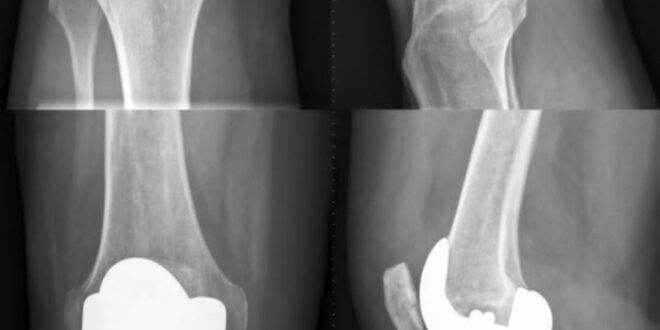

Osteoarthritis can be divided into four different grades, depending on the level of degeneration of the joint. The grading goes from grade 1 to grade 4, with grade 4 being the most severe. The grading is done on the basis of X-ray. Usually, joint replacement is done in patients with grade 4 osteoarthritis. When the cartilage between the bones in the joint is completely worn out, it leads to severe pain and even knee deformation. That’s a grade 4 osteoarthritis, and it needs surgery. Although, sometimes, surgery is also done in grade 3 patients.

During the surgery, the degenerated part of the knee is removed, and the cartilage is replaced with a cobalt chromium alloy. The wear and tear on this alloy is very low, and it has an average lifespan of around 20 years. A highly compressed plastic called poly is also used between the metal alloy pieces to ease the movement of the joint after surgery.